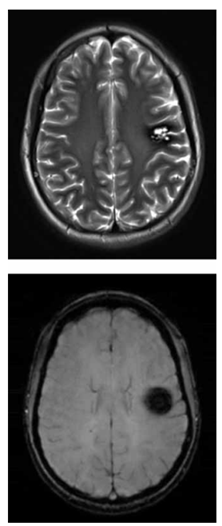

Adolescente de 16 anos realiza exame de imagem por

ressonância magnética do crânio para investigação de

epilepsia focal. O exame demonstra a alteração a seguir

(imagem ponderada em T2 e imagem ponderada em suscetibilidade magnética (SWI), respectivamente):

(Arquivo pessoal; imagens usadas com autorização)

Considerando o exposto, é correto afirmar que o achado das imagens é compatível com